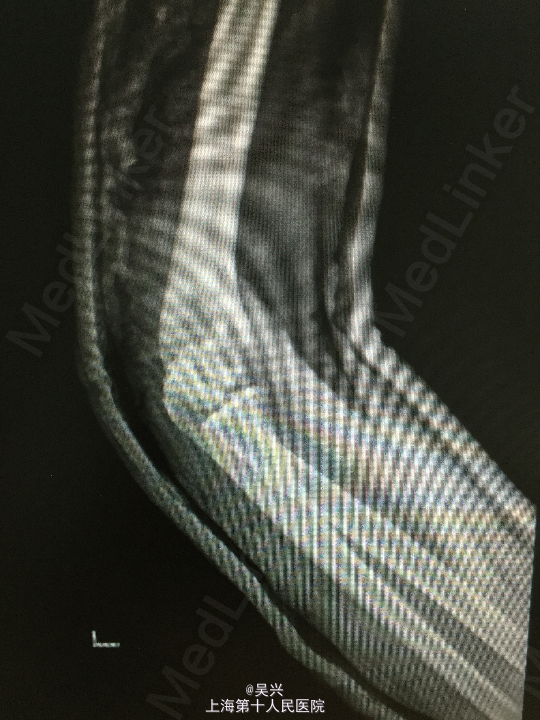

诊断:左肘恐怖三联症。 处理:术前准备,抗炎消肿治疗,术后三天行左肘正中切口显露尺骨冠状突,术中见尺骨冠状突粉碎性骨折,用两枚微型空心螺钉固定,发现屈肘位置仍有肘关节半脱位趋向。予伸肘位石膏固定,术后2周改屈肘45度位石膏固定,术后4周拆石膏,能逐渐屈肘至90度。

随访:术后1月患者肘关节稳定性良好,伸肘0度,屈肘90度,理疗辅助功能锻炼中。 讨论:肘关节脱位(半脱位)伴尺骨冠状突骨折、桡骨小头骨折称为肘关节恐怖三联症。该症存在极度肘关节不稳定,容易发生向后方、侧方脱位。一般单纯尺骨冠状突骨折极少,多伴有桡侧结构损伤和关节不稳定。肘关节恐怖三联症治疗原则一般是复位固定尺骨冠状突和桡骨小头,修复桡侧副韧带。我们术中发现固定尺骨冠状突后关节仍然不稳定,但桡骨小头因不全骨折需要石膏固定,因此不采取手术修复外侧副韧带,而是石膏固定,术后也取得较好的效果。